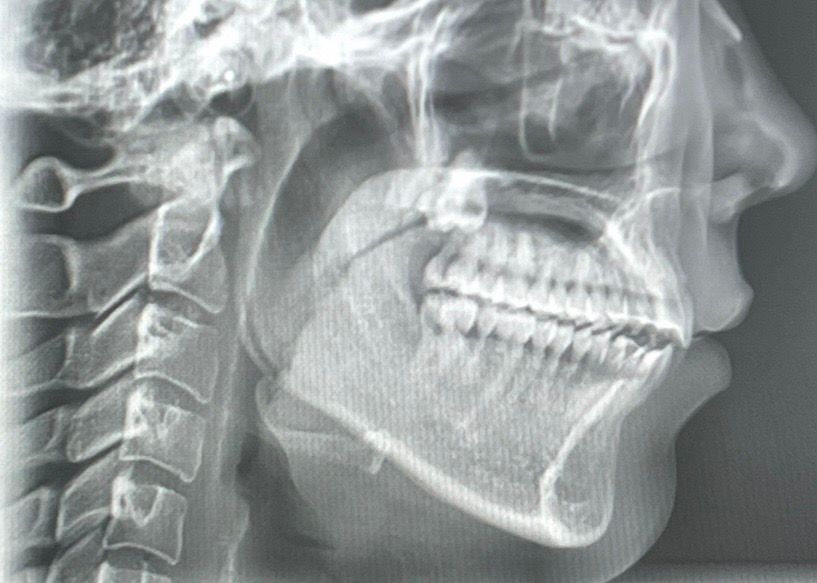

제가 19~21년 치아교정하고 정말 예쁜 교합으로 잘 지내다가 올해 3월 초에 질긴 음식을 먹고 3월 중순 쯤 자고 일어났더니 오른쪽 턱관절이 뒤로 밀려서 (회전해서),개방교합이 생겼습니다. 디스크 쪽 불편함도 있어서 구강내과 치료도 받다가 호전이 없어 구강악안면외과에 갔더니 제가 턱 사이즈가 작은데 , 턱이 뒤에 있어야 편한 위치인데 치아교정은 앞에서 물리게 해놔서 질긴 음식 먹은 충격으로 인해 뒤로 밀린거라 하셔서 하악 수술을 하라고 했는데 아무리 생각해도 너무 의아해서요. 턱 사이즈가 작다고 어느날 이렇게 뒤로 밀리는 일이 생기나요? 저는 아무리 봐도 디스크가 어긋나서 막고있는 것 같아요 CR CO Discrepancy를 언급하시던데 저는 치아교정한 교합으로 정말 편하게 지냈거든요

사진은 순서대로 턱 뒤로 회전하기 전,후입니다.

3. 현재 엑스레이 사진상으론 어금니 교합은 정상적입니다. 치아 교합보다는 턱관절 문제에 집중해봐야 할 것 같습니다